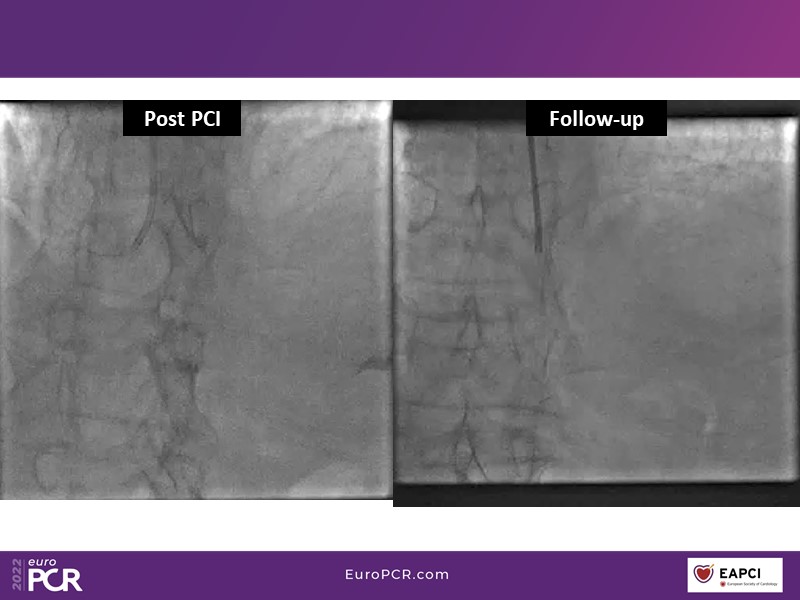

- To find out more about the application and mechanism of a sirolimus coated balloon for coronary artery disease treatment with case presentations in complex settings

- To understand how useful is a DES and DCB stent platform in complex coronary artery disease settings with case demonstrations and follow-up in diabetes mellitus